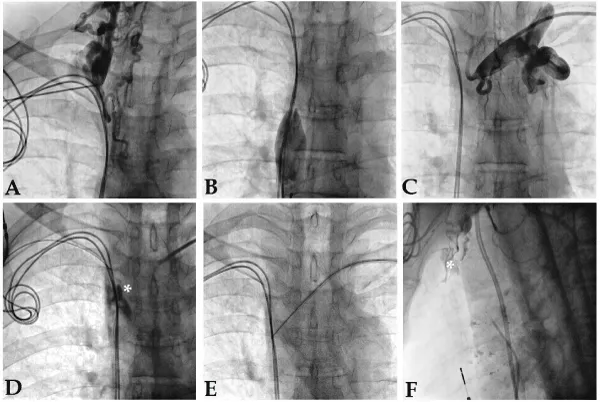

A 49-year-old gentleman was admitted to our hospital with episodes of presyncope/syncope due to complete heart block in 2010. He underwent a DDDR (REDR01-RELIA, Medtronic, USA) pacemaker implantation via right subclavian route uneventfully. In 2015, his symptoms recurred due to ventricular undersensing and non-capture by insulation failure of ventricular (RV) lead. Lead replacement was planned, but to our dismay, SVC was found completely occluded (Figure 1A,C). Percutaneous recanalization of SVC and lead extraction via femoral route failed, as wire always ended up in false lumen (Figure 1D) and dense fibrosis prevented lead mobilization. In another sitting, recanalization was attempted by transseptal puncture needle via left subclavian route, but was abandoned due to a small self-contained SVC perforation (Figures 1E,F). Finally, he underwent surgical epicardial RV lead placement and pulse generator was implanted in left subpectoral region.

Figure 1: Complete SVC occlusion (A-C). Recanalization failed despite attempted balloon dilation (D), transseptal needle puncture via femoral route, and transseptal needle puncture via left subclavian route (E) – which created a contained perforation (F).